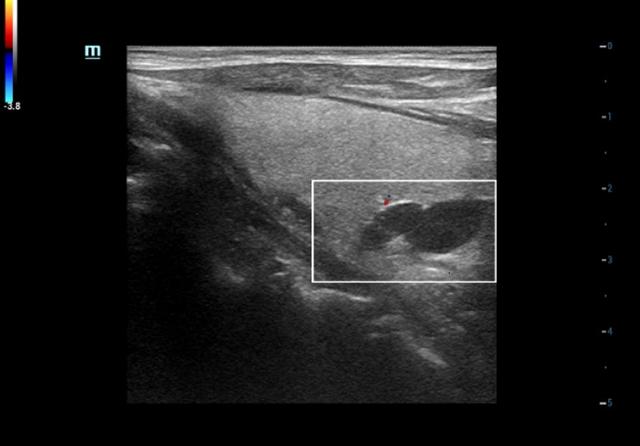

治疗前甲状腺旁腺素非常高(3300pg/ml),血钙正常,超声显示双侧甲状腺旁腺明显增大(如下图),核素扫描显示甲状旁腺功能亢进性骨代谢异常性骨病(骨骼变形)。

介入微创消融治疗时,将功能亢进的甲状旁腺原位灭活(如下图)